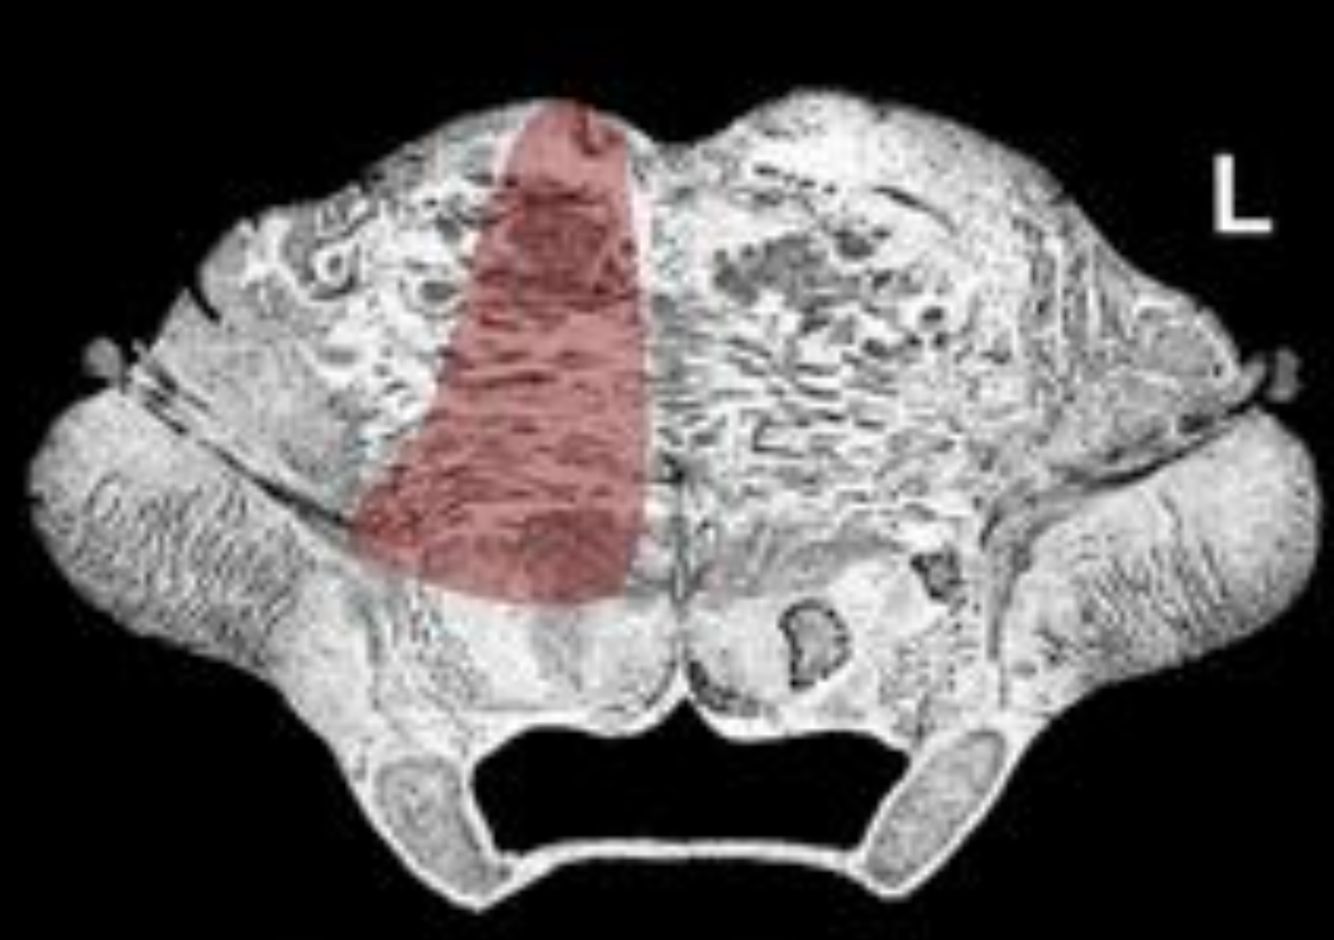

What is the name/location/results of the condition caused by a lesion in the shaded area?

Midbrain/Thalamus at Posterior Commissure

Alternating Oculomotor Hemiplegia (Weber’s Syndrome)

Destruction of the oculomotor nerve results in external strabismus, pupillary dilation and

complete ptosis.

Destruction of the corticospinal tract results in contralateral spastic hemiplegia.

Destruction of the substantia nigra may result in contralateral resting tremor.

Destruction of the uncrossed corticobulbar tract contralateral brainstem motor nuclear palsies, including supranuclear facial palsy.